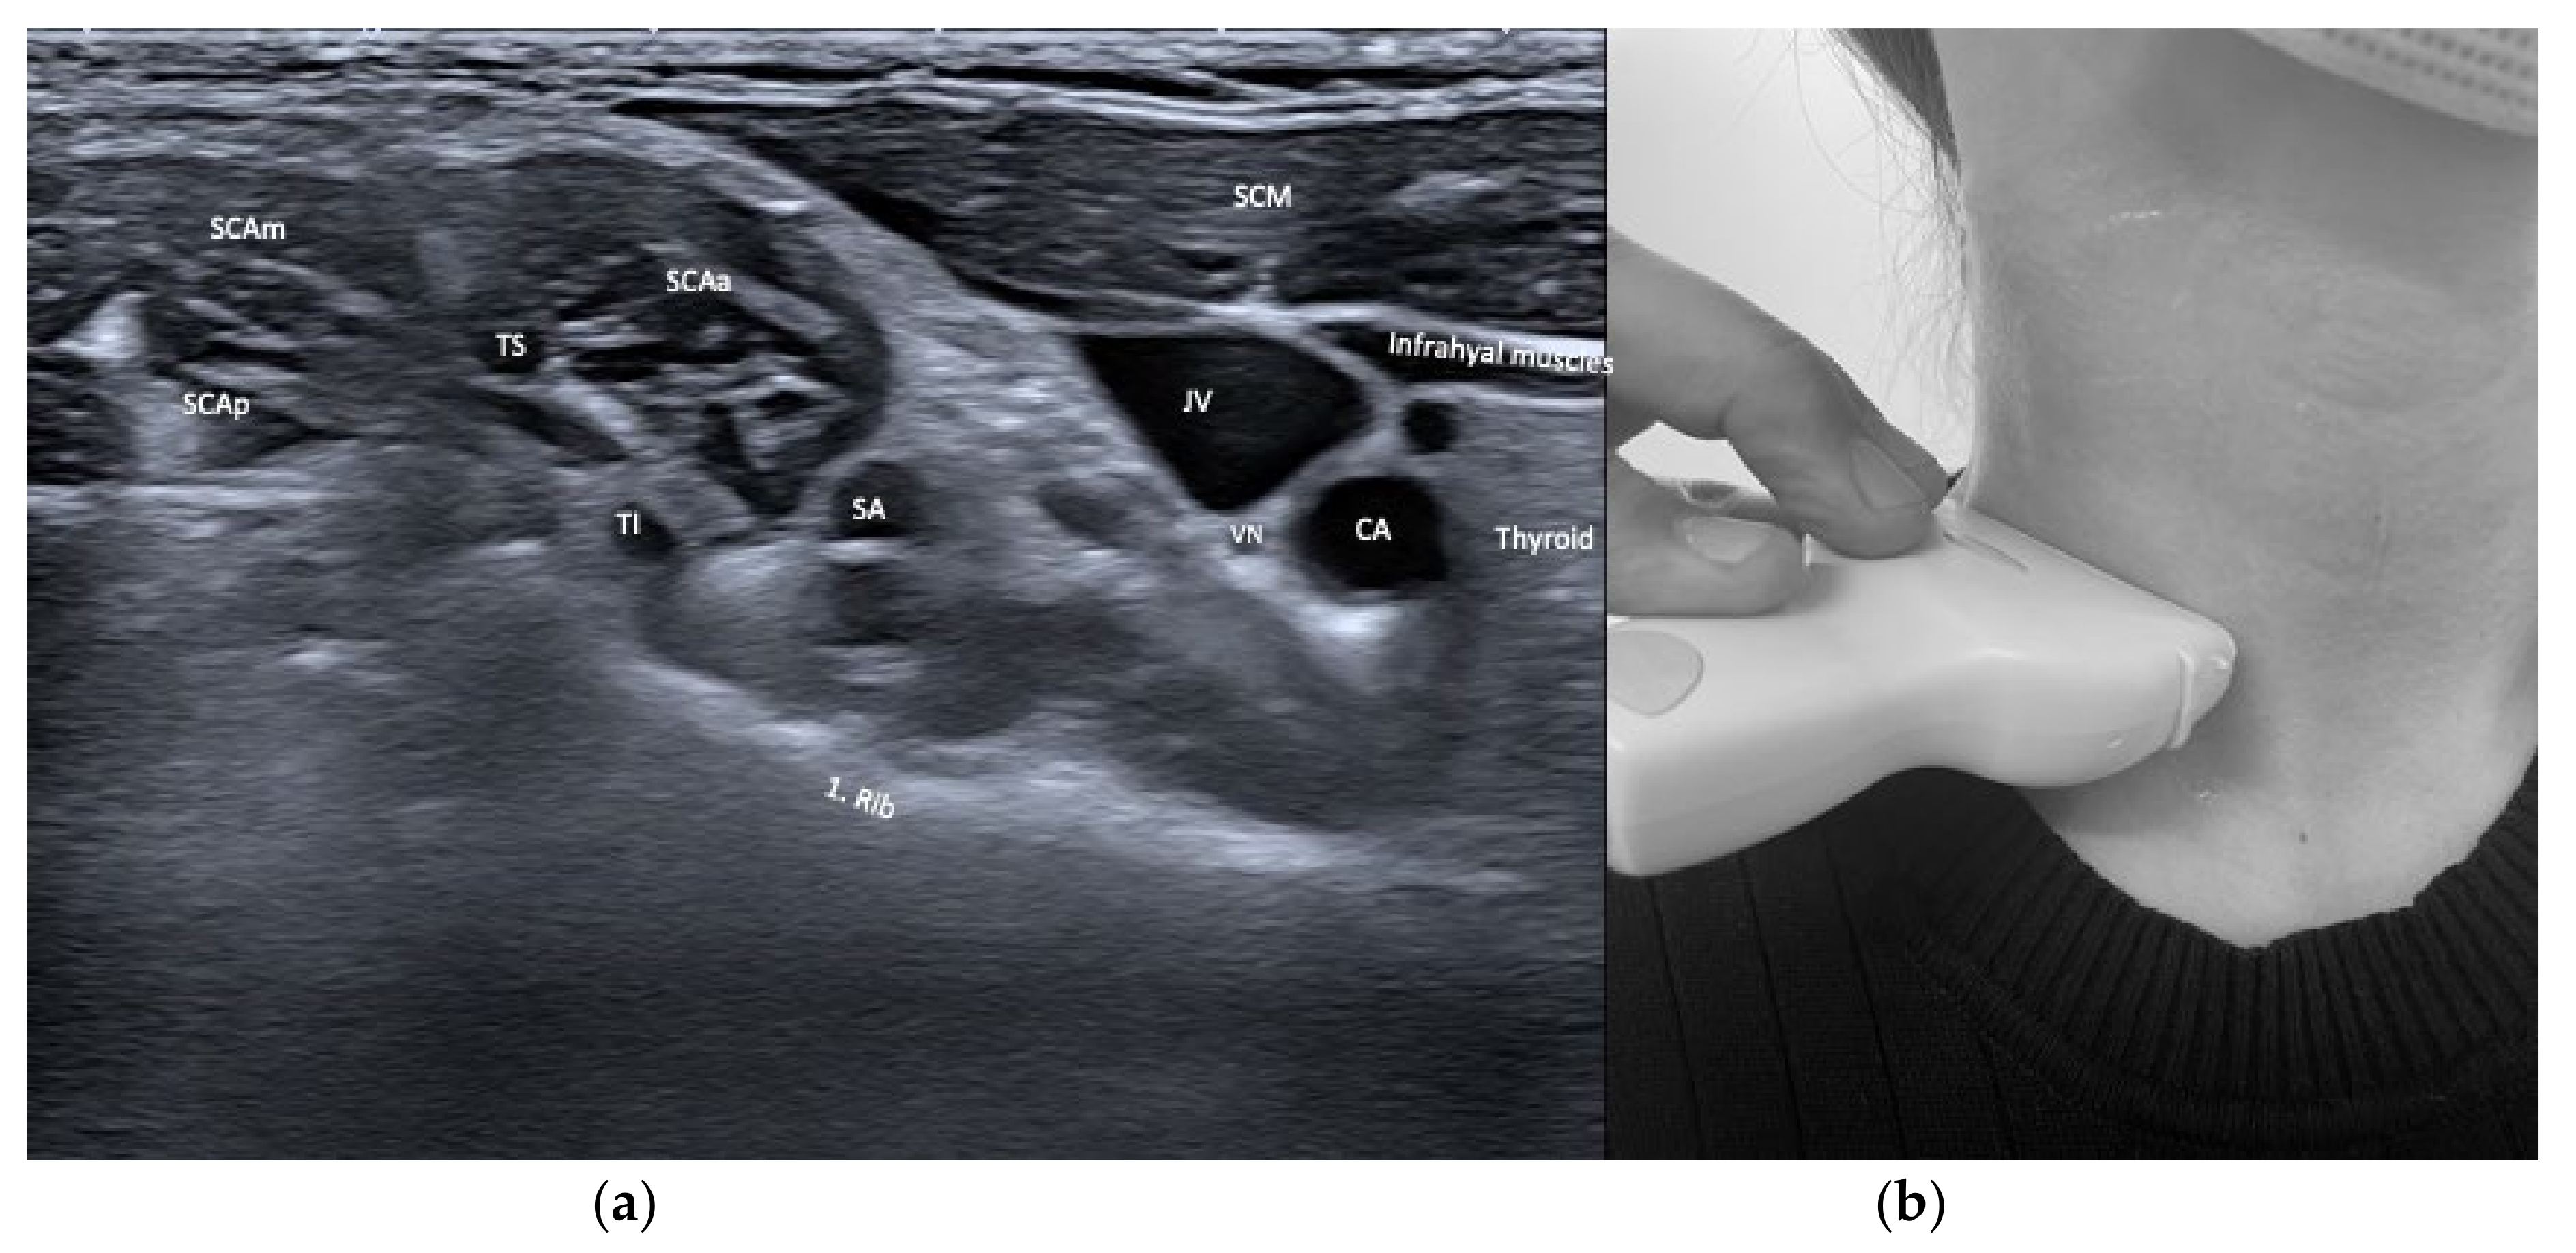

| Scalenus anterior (SCAa) | Anteflexion of neck | +++ | +++ | Thyroid, carotid artery, brachial plexus, phrenic nerve, lung | |

| Scalenus medius/posterior (SCAmp) | Ipsitilt of neck | ++ | ++ | Brachial plexus, lung | |

| Sternocleido-mastoid (SCM) | Contraversion of head and neck Ipsitilt of head and neck Anteflexion of head and neck with bilateral activation | + | ++ | Infrahyoid/supra-hyoid muscles, omohyoid, carotid artery, jugular vein | Dysphagia (particularly if injected bilaterally) |